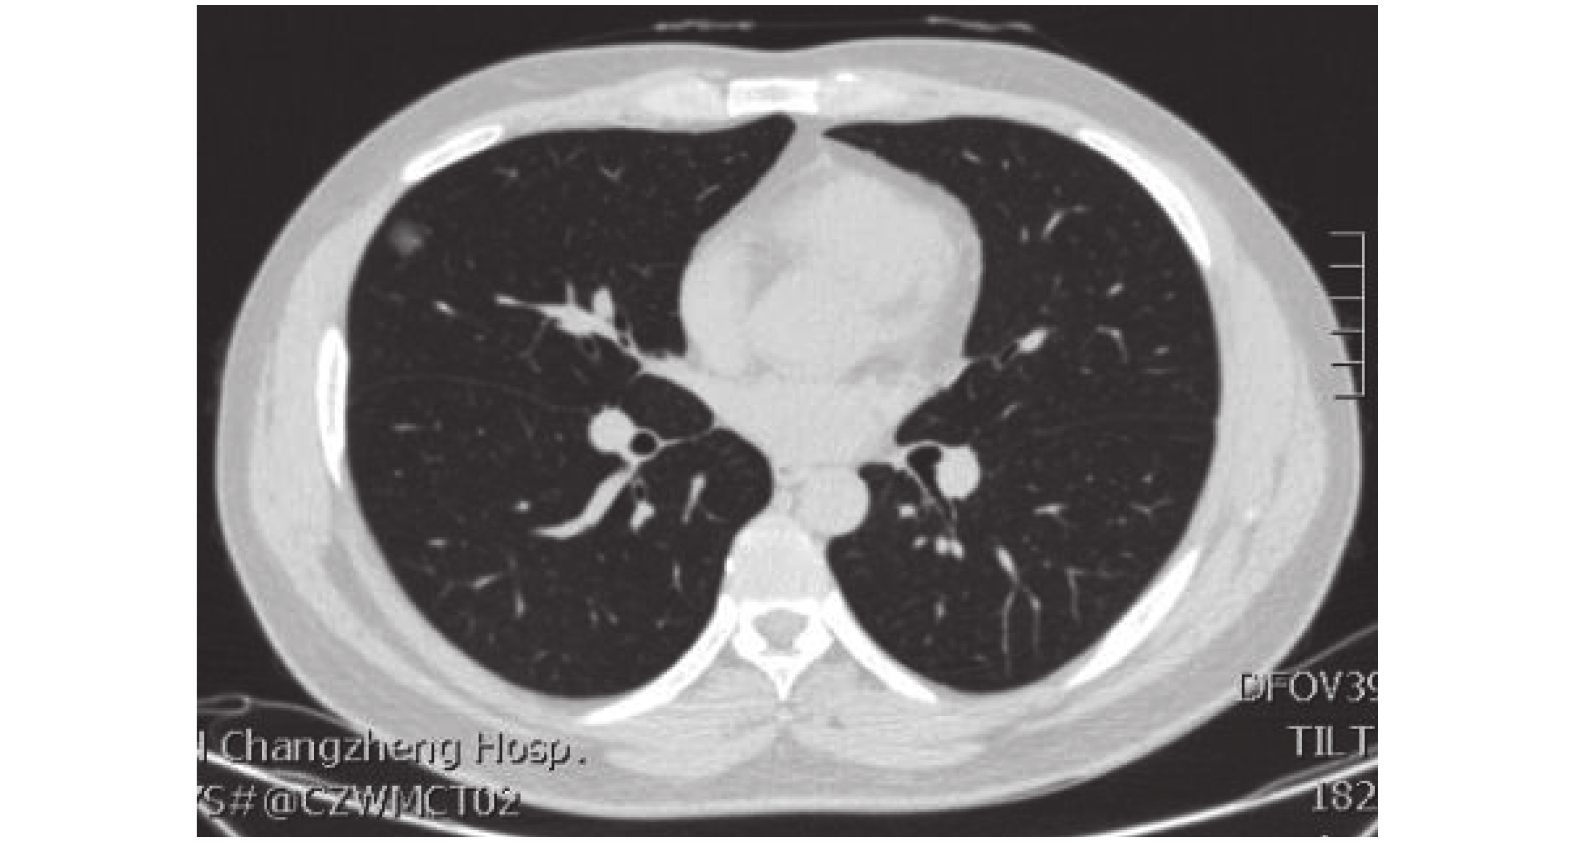

臨床資料 患者,男,30 歲,右肺中葉外側段結節,大小約 5.5 mm,見圖 1。納入標準:術前胸部 CT 提示懷疑早期肺癌,且肺結節大小在≤1 cm,術前吲哚菁綠(indocyanine green,ICG)皮試陰性,無肝腎功能不全。排除標準:既往 ICG 過敏,對碘化物過敏,甲狀腺疾病,腎臟或腎臟的過敏素質肝功能衰竭,懷孕或哺乳期。本研究經我院倫理委員會批準,患者家屬術前簽署手術知情同意書。近紅外熒光成像系統使用 easyScopy NIR/ICG 醫用熒光內窺鏡攝像系統(上海逸思醫療科技有限公司),可在白光模式和近紅外光模式下自由切換。注射用 ICG 為 25 mg/支(衛材(遼寧)制藥有限公司)。